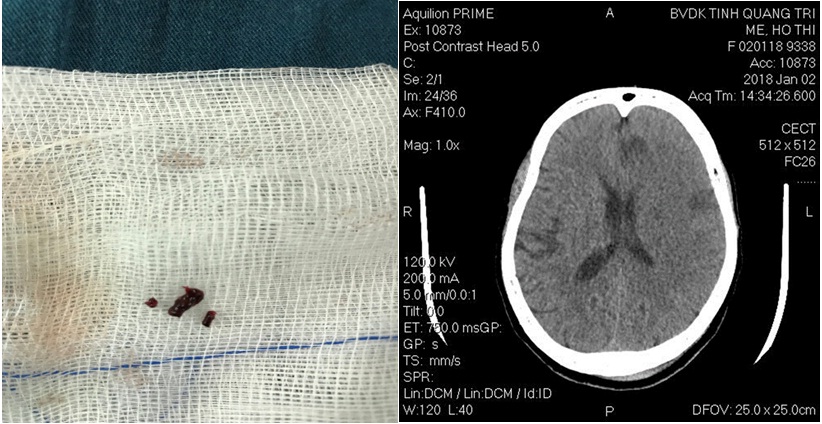

Hình: Các cục huyết khối được lấy ra và hình CLVT sọ não sau 2 ngày.

- Sau can thiệp B/N liệt cải thiện (cơ lực tay chân 3/5)

Hình: Sau lấy huyết khối hoàn toàn Cảnh trong và M1 trái và các cục huyết khối được lấy ra.

- Sau can thiệp bệnh nhân tỉnh táo, Glasgow 14 điểm, cải thiện liệt với cơ lực tay chân 4/5.